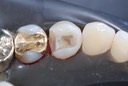

Photos of Clinical Operations

Drs. Peter Kearney, Terry McKay, John St. Germain, and Laurie Vanzella - Mentors